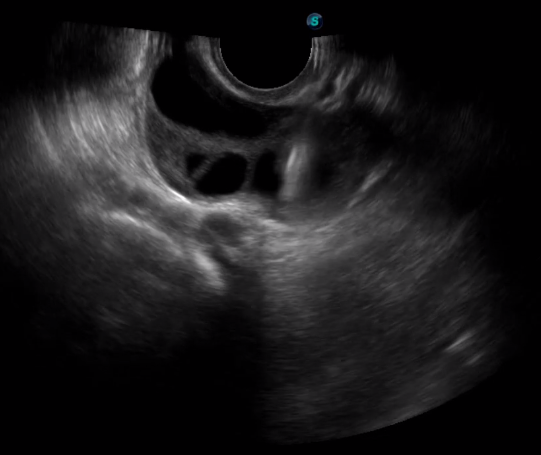

傳統(tǒng)腔內探頭采用直柄設計,在搭配穿刺架使用時,手術空間小,不易操作;生殖專用的曲柄探頭,探頭柄采用彎曲成角度設計,可實現監(jiān)視、取卵兩不誤,搭載穿刺架時,可以清晰顯示穿刺針的進針過程、深度和位置,實時監(jiān)視取卵全過程,保障取卵操作精準與安全。

取卵臨床圖

多數的生殖科醫(yī)生對于受精卵的植入采用憑經驗操作或是使用傳統(tǒng)腔內探頭引導,同樣存在手術空間小、受精卵放置位置不確定等風險。專業(yè)的宮腔專用探頭,配合專用的窺器使用,為醫(yī)生提供最大的手術視野。

胎移植臨床圖